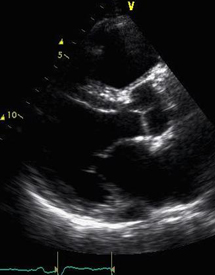

Valvular heart disease results in a murmur which can be detected when a doctor listens to the heart although murmurs can occur in normal hearts as well. The most common test to look at whether there is significant valve disease is an echocardiogram which is similar to an ultrasound scan that is used to look at babies before they are born. The treatment for valvular heart disease depends on the type of valve disease and the effects that it has on your heart.

Below is an example of a heart MRI scan.